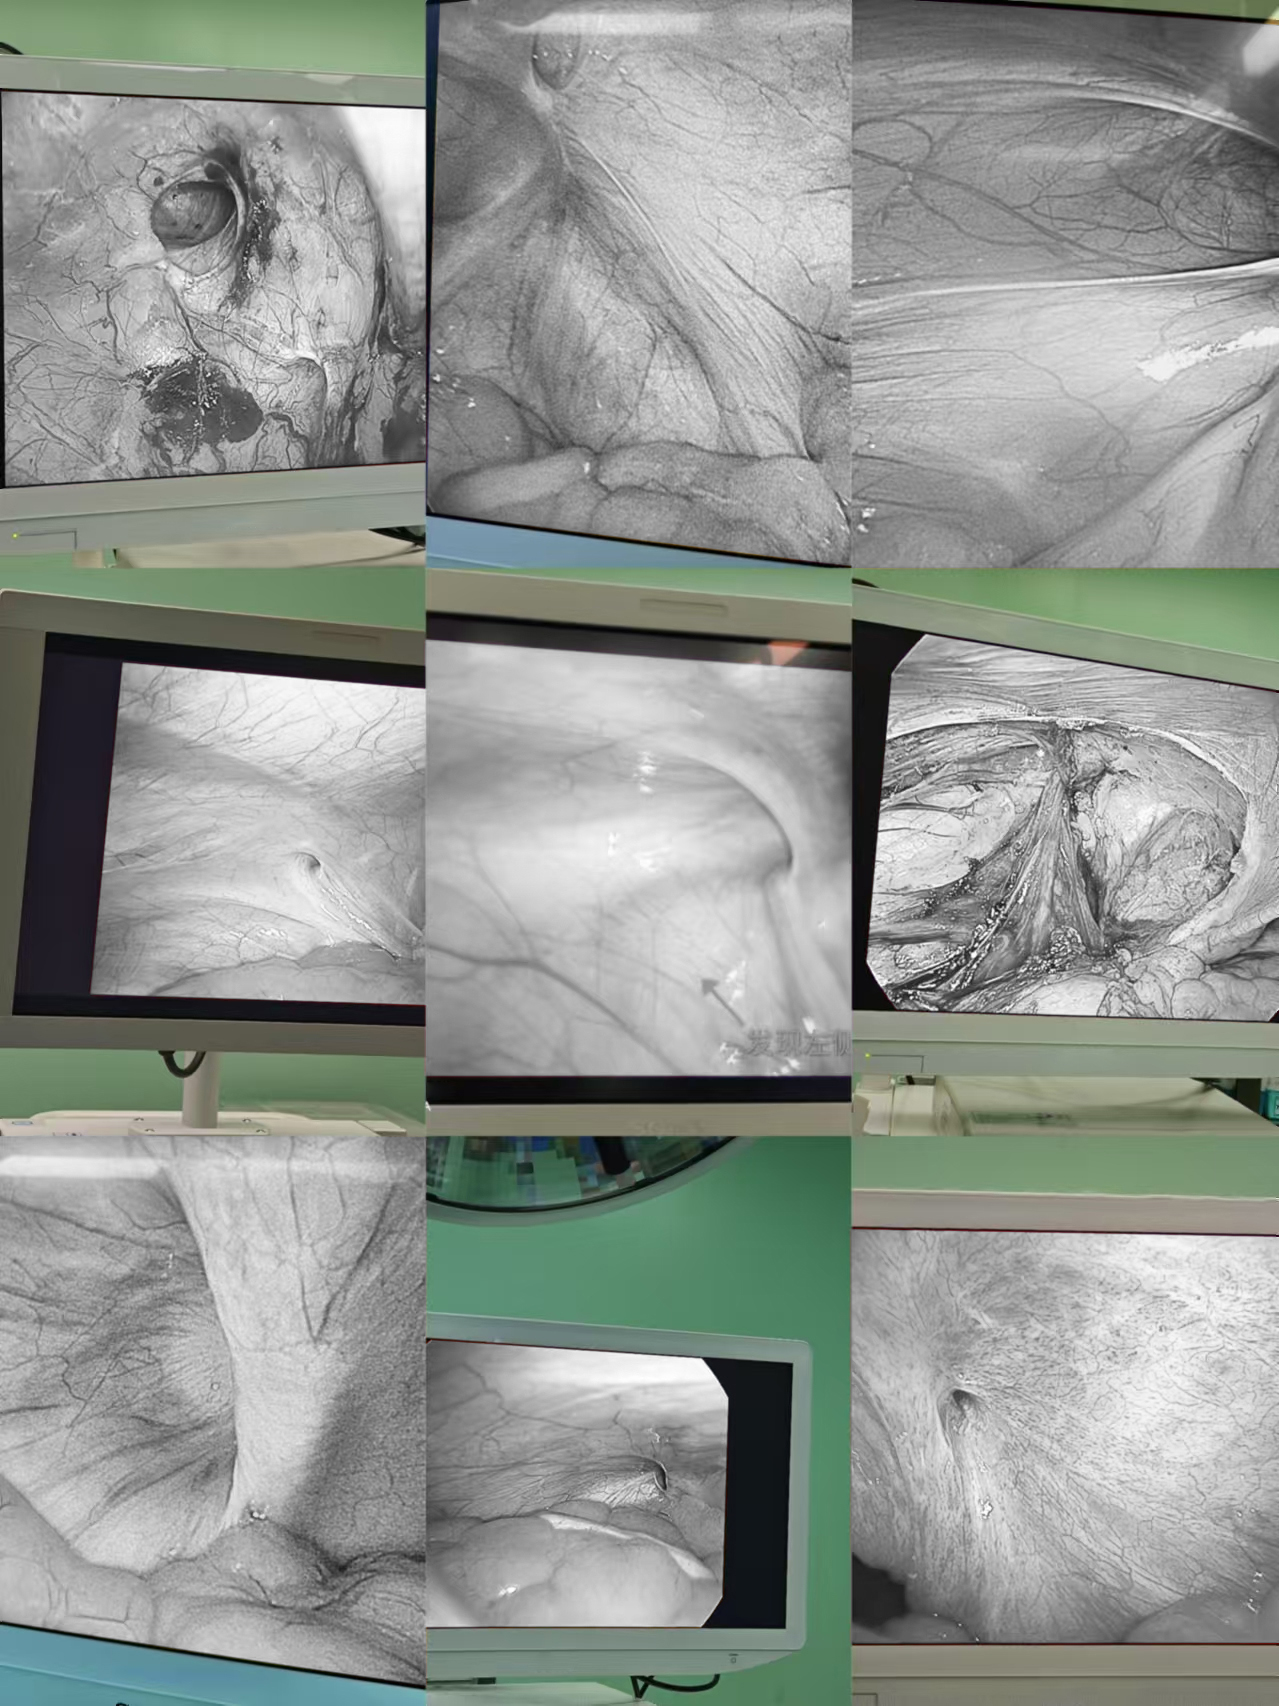

照片已部分黑白化处理,点击仍需谨慎

各种不同炎症阑尾炎

照片已部分黑白化处理,点击仍需谨慎

各种不同炎症胆囊结石

照片已部分黑白化处理,点击仍需谨慎

各种不同原因的胃肠脾破裂

照片已部分黑白化处理,点击仍需谨慎

各种不同的疝

照片已部分黑白化处理,点击仍需谨慎